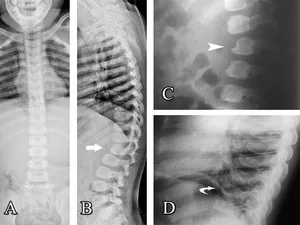

- Dysostosis multiplex: oar-shaped ribs, bullet-shaped phalanges, anterior vertebral beaking.

- Kyphosis (gibbus deformity), hip dysplasia, carpal tunnel syndrome.